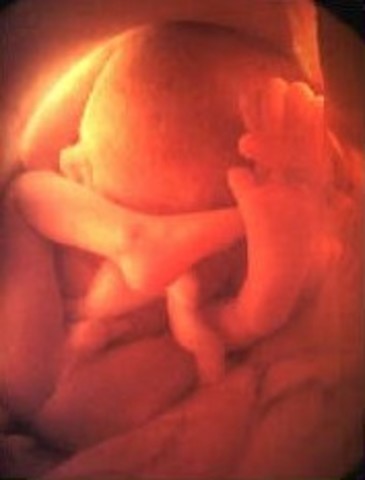

• Week 26 end of second trimester

Week 26 end of second trimester

The baby is more responsive to touch, and the babies muscles become more coordinated and it starts moving around in the womb. The baby has the ability to suck it's thumb which strengthen the jaw muscles, at this time the baby is 14 inches long and weighs around 1.7 pounds.

Fact: you can play with the baby by touching on your stomach